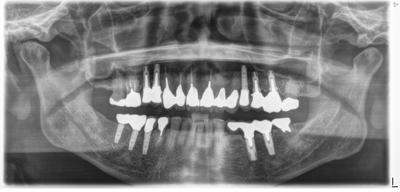

2020.12.26インプラント包括ケース

初診は20年程度前。包括診療ケース。

メインテナンスを続けていたが、歯ぎしり、TCHが強く歯根破折を起こして3回位に分けて徐々にインプラントが増加。

最初から包括診療で理想的な咬合関係を構築しているため、破折で保存不可能と判断されても、同部の抜歯インプラント治療のみで対応可能。

インプラントが咬合をしっかり支えてくれている。